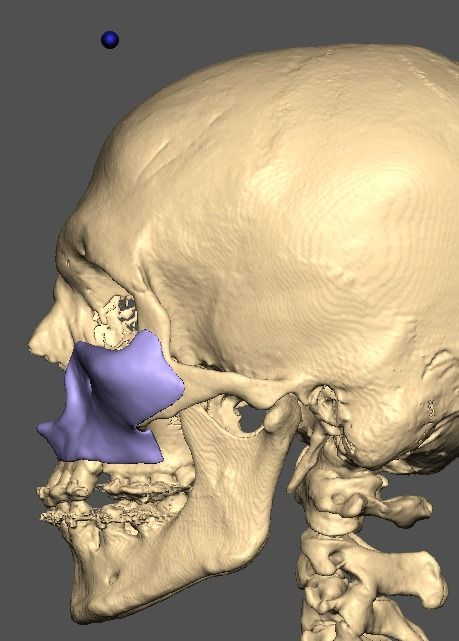

A lot changed since the initial design

It's going to be split into either 5 or 7 pieces.